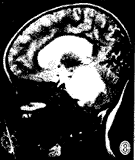

MRI:鉴于无颅骨伪影和多方位成像特点,MR是目前诊断胶质瘤和准确定位的最好方法,对于治疗计划的制定和随访有很大帮助,特征性MR表现为脑干胶质瘤呈膨胀性生长(图1~3),多为实质性,在T2加权图像上显示最为清楚,为明显高信号(图3),在T1加权图像上为低信号或低、等混合信号(图4),注射GD-DTPA后多数病灶 明显增强,少数无明显增强(图1~2),强化方式有:弥漫型(图未列出)、结节型(图4 ~6),沿着肿瘤边缘或囊变坏死区呈环状(图7)。肿瘤边界多较清楚,周围脑组织水肿多 较轻或不明显,肿瘤内部可发生小囊变或小出血灶,肿瘤向前生长包埋基底动脉(图1~3) ,部分脑干胶质瘤可位于中脑导水管附近,虽然较小,但可造成对中脑导水管的压迫,而继 发脑积水[3](图8),MRI较CT能更好地明确占位性病变的性质、部位、范围。

图1-3 女性,5岁,脑干明显增大膨突,横断面T1W低信号(图1),T2W高信号(图3),无明显强化(图2),肿块向前包绕基底动脉,向后推移第四脑室。图4-6 女性,6岁,横断面T1W低信号(图4),矢状面T1W增强(图5), 横断面T1W增强(图6),片状不均匀强化灶中见结节样强化。图7 男 性,6岁,横断面T1W增强,肿块环状强化呈葫芦形,中央低信号灶不强化。图8 女性,2岁,矢状面T2W,肿块向后压迫中脑导水管,第三脑室、侧脑室积水明显。